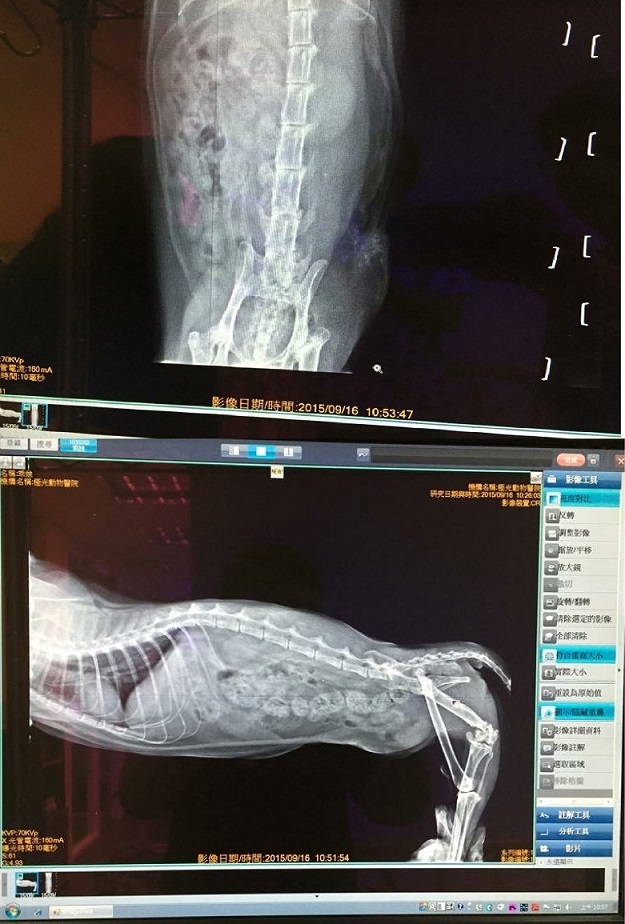

主題: 癱瘓肢側有不明腫塊的乖妹 申請者姓名: 臺北市支持流浪貓絕育計劃協會 花色: 申請日期: 2015-10-20 15:31:08 申請者部落格: 申請者臉書網址: 所在縣市/合作醫院: 台北市/其他院所醫助專案(醫院請先MAIL溝通) 治療費用: 18000元 需求人數: 18人 已結案 (2022-05-13 15:11:33) 報名人員: 小四(已付款)、Wendy Cheng(已付款)、陳宣蓉(已付款)、daisy lu(已付款)、張恩綺 x2(已付款)、Ray0322(已付款)、徐小安 x2(已付款)、elsa(已付款)、Peggy(已付款)、jojo(已付款)、J(已付款)、Pei-yan Wu(已付款)、陳良彥(已付款)、shuwenyeh(已付款)、廖小茜(已付款)、林佳筠(已付款)、 候補人員: 動物病情說明: 因為車禍癱瘓的乖妹, 是應了協會的照顧以及生活, 雖然後軀癱瘓, 但乖妹仍用前肢撐起身軀, 靈活的移動, 跟安養之家的其他貓咪為伴.

但在9月份, 無意中在乖妹癱瘓的左後軀發現了約半個拳頭大的不明腫塊,

送醫檢查, 腫塊呈現的是大量的發炎脂肪細胞以及嗜中性球跟單核球,

因為在貓身上發現含這類細胞的腫塊, 之後轉變成腫瘤的可能性非常高,

顧安排手術切除, 以絕後患.動物近況說明: 因為腫塊大且深, 而必須將腫塊由限界切除乾淨,故開刀的範圍既深且大, 傷口長達近15公分,